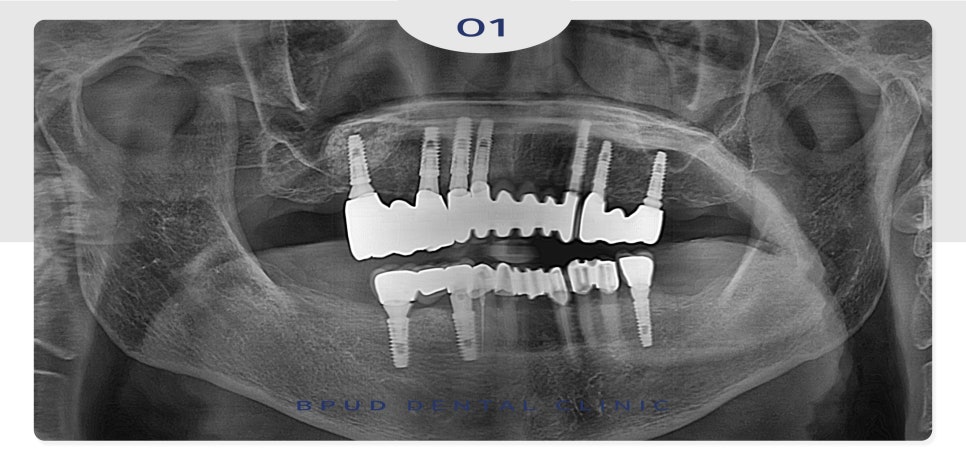

23.09.11

최종 보철물까지 완료한 모습입니다.

처음에는 예산 문제로 인해 걱정이 많으셨지만

필요한 개수만큼만 식립하여 비용은 줄이고

만족도가 너무 높으시다며 심미적이고

식사하실 때도 틀니보다 너무 편하고

좋다고 하셨습니다.